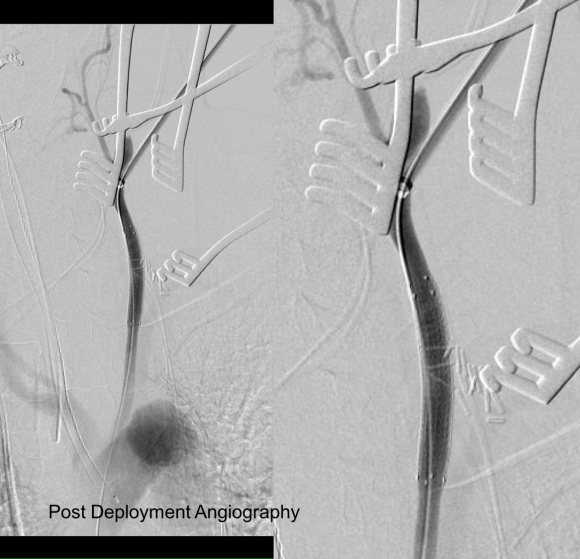

The smallest stent graft we have is a 21mm graft, but it would not be suitable for this aorta. In practice, the normal aorta is quite elastic and will dilate much more than what is captured on a CTA. The next size we have is 28mm graft and I chose this to exclude the rupture, which was done percutaneously.

As seen below, the graft excluded the celiac and SMA. Late in the phase of the final aortogram (second panel) there was an endoleak that persisteed despite multiple ballooning. The timing suggested the intercostals and phrenic vessels contributed to a type II endoleak, but it was concerning.

This worked to relieve the kink as evidenced on the aortogram above. After closing the laparotomy, I placed a chest tube in the right chest. The patient had a course prolonged by a classic systemic inflammatory response syndrome, with fevers, chills, and leukocytosis. He bled for a while but stopped with correction of his coagulopathy. All blood cultures were negative, but a CT scan was performed out of concern for the endoleak, and the possibility of continued bleeding.